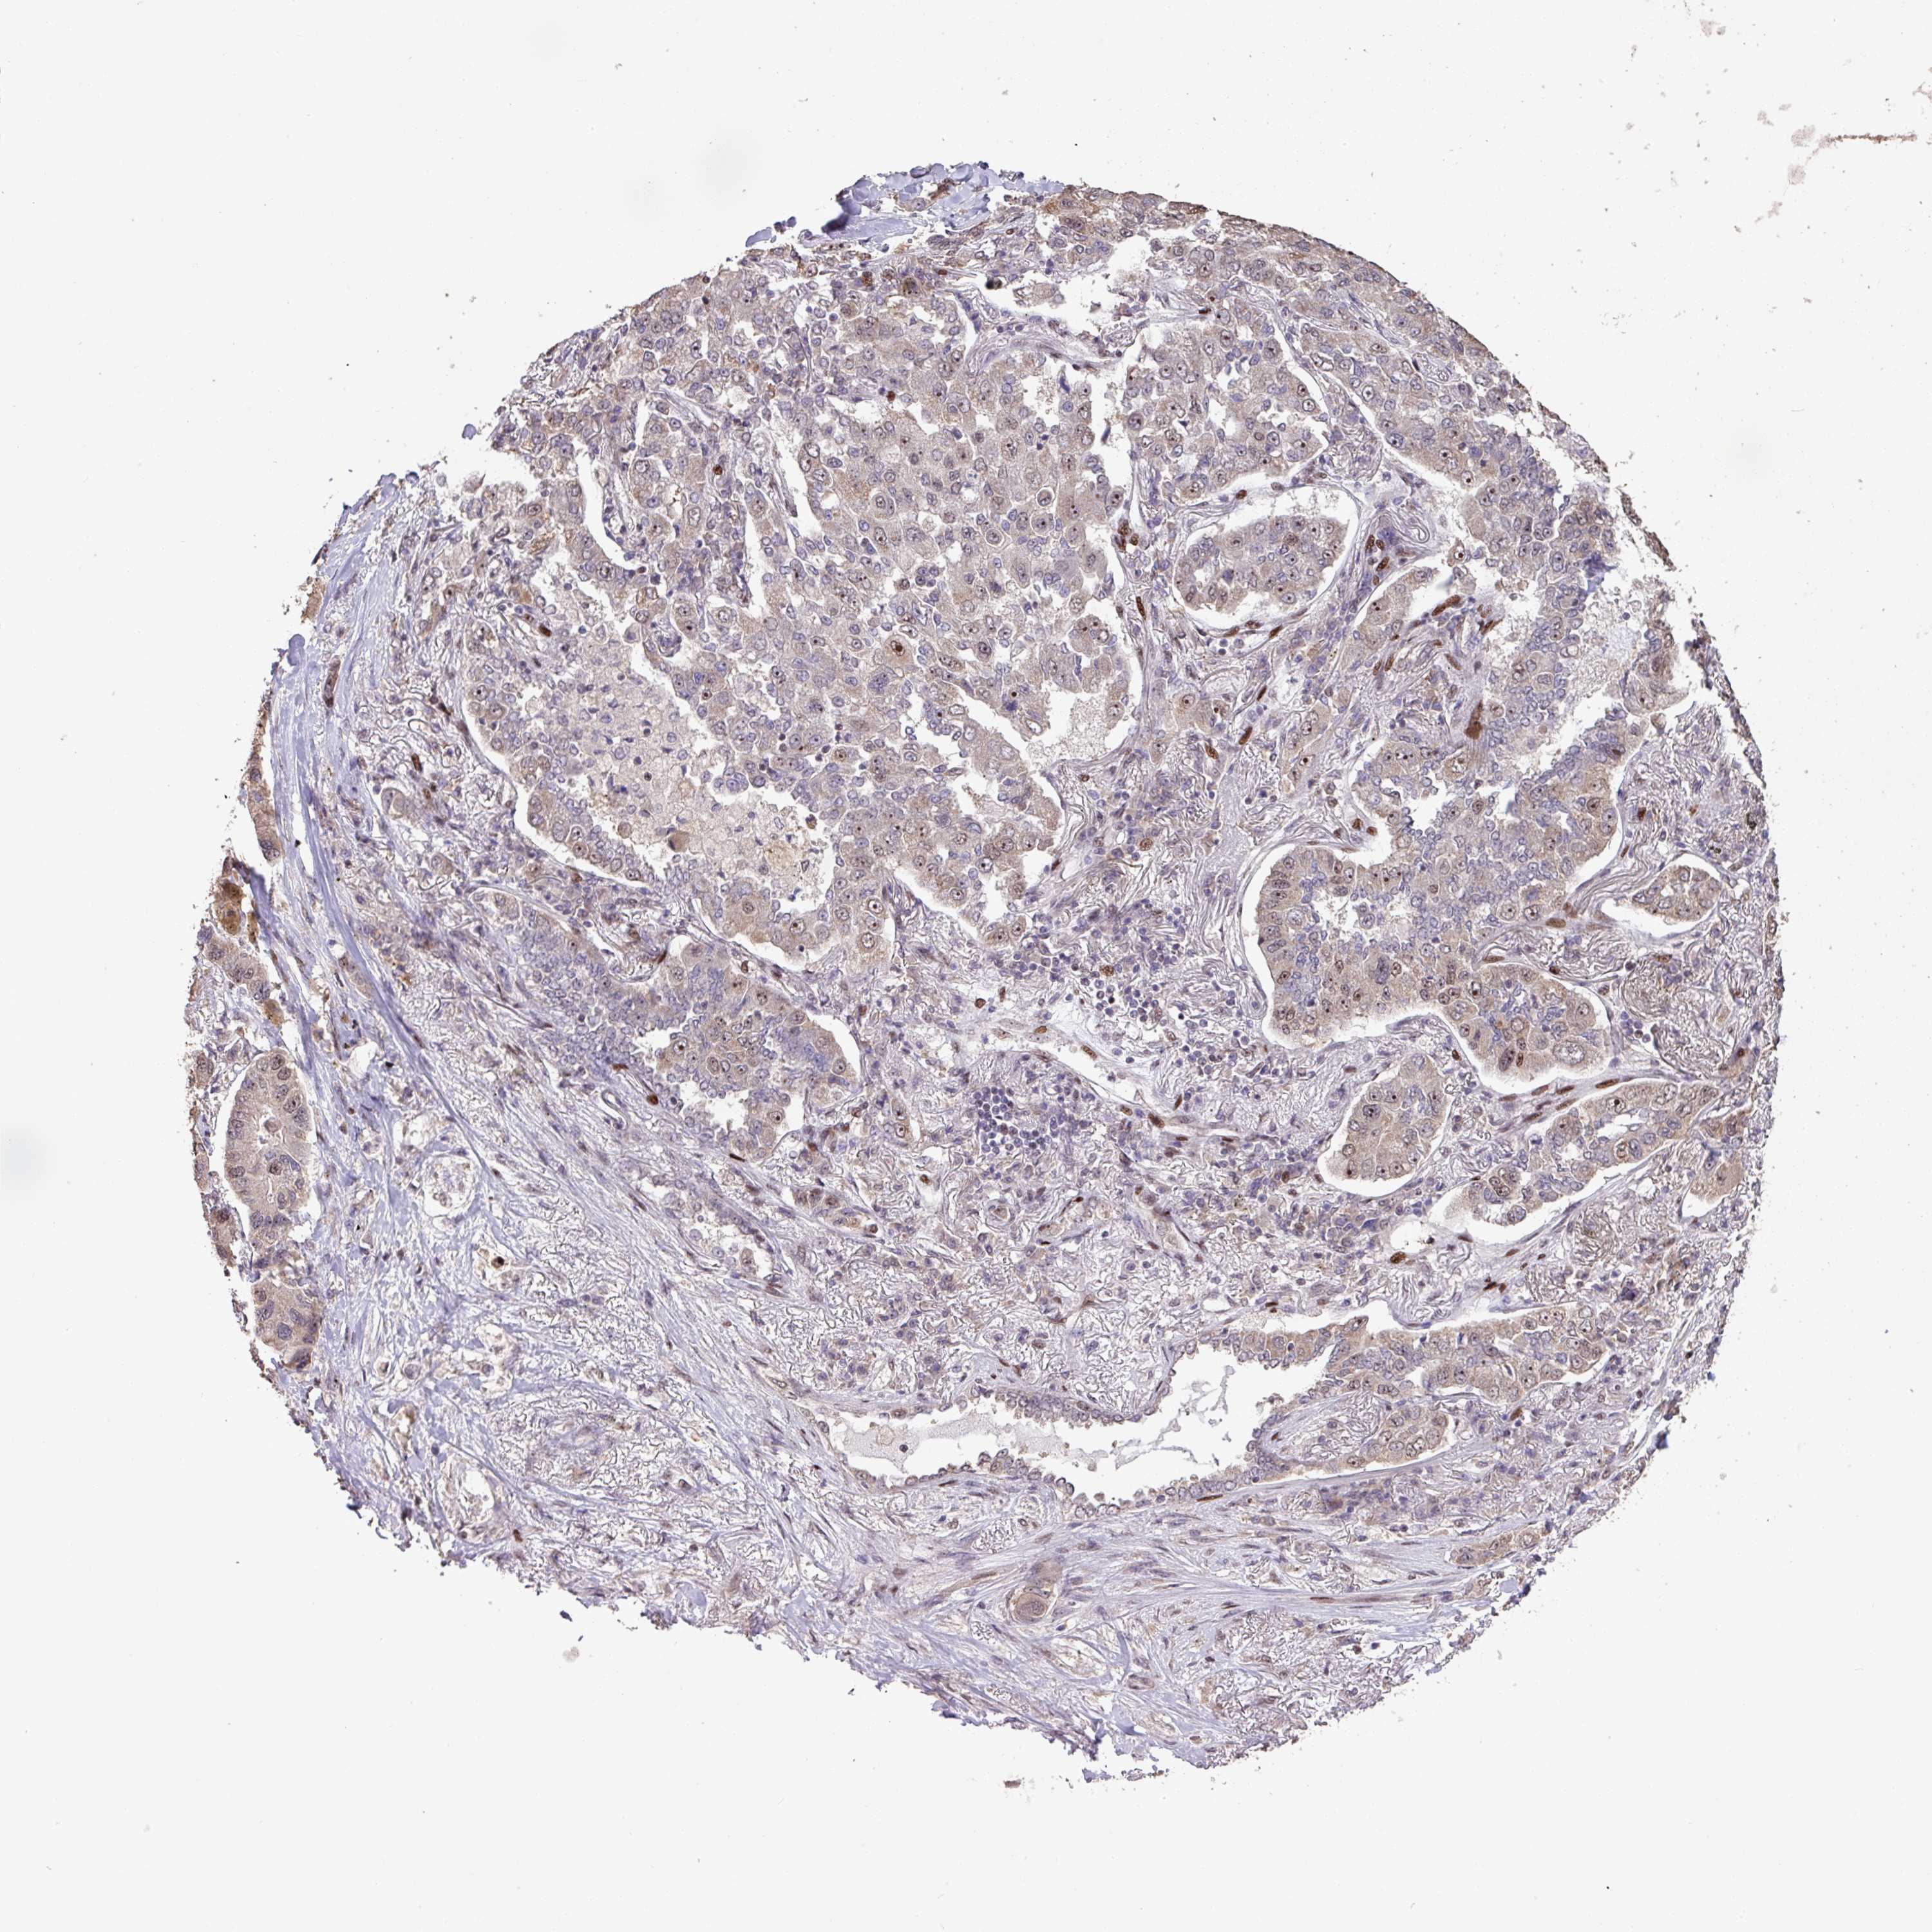

LUNG ADENOCARCINOMA (VALIDATION) - Interactive survival scatter ploti

The Survival Scatter plot shows the clinical status (i.e. dead or alive) for all individuals in the patient cohort, based on the same data that underlies the corresponding Kaplan-Meier plots. Patients that are alive at last time for follow-up are shown in blue and patients who have died during the study are shown in red.

The x-axis shows the expression levels (FPKM) of the investigated gene in the tumor tissue at the time of diagnosis. The y-axis shows the follow-up time after diagnosis (years). Both axes are complimented with kernel density curves demonstrating the data density over the axes. The top density plot shows the expression levels (FPKM) distribution among dead (red) and alive patients (blue). The right density plot shows the data density of the survived years of dead patients with high and low expression levels respectively, stratified using the cutoff indicated by the vertical dashed line through the Survival Scatter plot. This cutoff is automatically defined based on the FPKM cutoff that minimizes the p-score. The cutoff can be changed by dragging the vertical line or by entering a cutoff value in the square labeled "Current cut-off".

Under the Survival Scatter plot the p-score landscape (black curve; left axis) is shown together with dead median separation (red curve; right axis). Dead median separation is the difference in median mRNA expression between patients who have died with high and low expression, respectively. It is calculated as follows: median FPKM expression of dead patients with high expression - median FPKM expression of dead patients with low expression. This is intended to aid the user in visually exploring custom cutoffs and the associated p-scores and dead median separation.

Individual patient data is displayed and can be filtered by clicking on one or more of the category buttons on the top of the page. Categories describing expression level and patient information include: high, low, alive, dead, female, male and tumor stages. The scale of the x-axis can be toggled between linear and log-scale by clicking on the "x log" button. Mouse-over function shows TCGA ID, patient information and mRNA expression (FPKM) for each patient.

& Survival analysisi

Kaplan-Meier plots summarize results from analysis of correlation between mRNA expression level and patient survival. Patients were divided based on level of expression into one of the two groups "low" (under cut off) or "high" (over cut off). X-axis shows time for survival (years) and y-axis shows the probability of survival, where 1.0 corresponds to 100 percent.

ZNF709 is not prognostic in Lung Adenocarcinoma (validation)

Best expression cut offi

Based on the FPKM value of each gene, patients were classified into two groups and association between prognosis (survival) and gene expression (FPKM) was examined. The best expression cut-off refers the FPKM value that yields maximal difference with regard to survival between the two groups at the lowest log-rank P-value. Best expression cut-off was selected based on survival analysis .

When clicking on this number, the vertical dashed line indicating cut-off, the interactive survival plot, and the Kaplan-Meier curve will be adjusted to show results based on the best expression cut-off.

: 0.83

P scorei

Log-rank P value for Kaplan-Meier plot showing results from analysis of correlation between mRNA expression level and patient survival.

N/A

TCGA RNA samplesi

RNA-seq data is reported as average FPKM (number Fragments Per Kilobase of exon per Million reads), generated by the The Cancer Genome Atlas (TCGA) .

Normal distribution across the dataset is visualized with box plots, shown as median and 25th and 75th percentiles. Points are displayed as outliers if they are above or below 1.5 times the interquartile range. FPKM values of the individual samples are presented next to the box plot.

Average pTPM 1.4

Number of samples 105